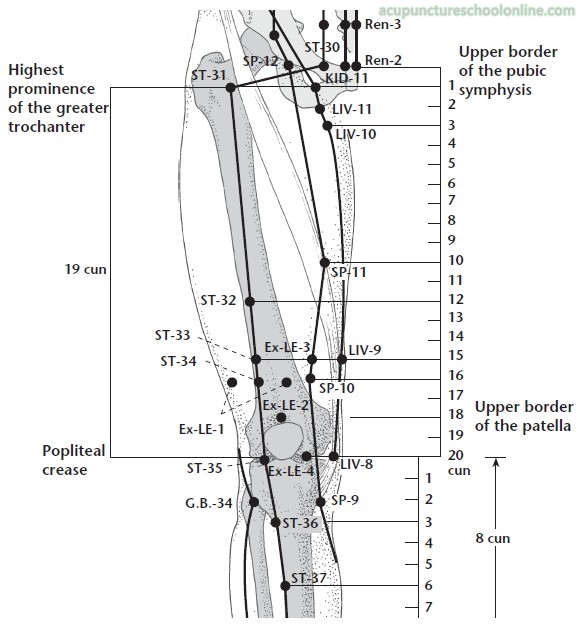

On the thigh, on a line drawn between the lateral border of the patella and the ASIS, in a depression 6 cun proximal to the superior border of the patella, or 1/3 of the distance from the superior border of the patella and the level of the greater trochanter, on the border of the lower and middle thirds.